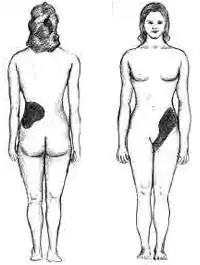

S'ils grandissent jusqu'à une taille relativement importante (de l'ordre de quelques millimètres), ils entraînent l'obstruction d'un uretère et la distension des cavités rénales par l'urine. Cela peut provoquer de violentes douleurs (dites « coliques néphrétiques »), siégeant en général au flanc et dans le bas abdomen.

Symptômes

La maladie est souvent détectée par l'expression d'une douleur typique, au moment d'un épisode d'insuffisance rénale avec colique néphrétique, mais d'autres types de douleur, une hématurie et/ou une infection peuvent aussi orienter vers ce diagnostic. Le caillou doit être activement supprimé dans 25 % des cas (soit une procédure de soins nécessaire pour 500 patients par million[6],[5][pas clair]).

La lithiase urinaire est habituellement idiopathique et asymptomatique jusqu'à ce qu'un calcul obstrue l'écoulement de l'urine. Les symptômes peuvent inclure une douleur aiguë du flanc (appelée colique néphrétique), nausée et vomissements, agitation, douleur sourde ou aiguë, hématurie, et fièvre en cas de surinfection. La colique néphrétique aiguë est décrite comme l'une des pires douleurs qui soient. Mais certaines personnes n'ont aucun symptôme jusqu'à ce que leur urine contienne du sang (hématurie), ce qui peut constituer le symptôme révélateur d'une lithiase rénale.

Plus rarement, lorsque la lithiase atteint les voies urinaires basses, elle peut se manifester par une difficulté à la miction (dysurie).